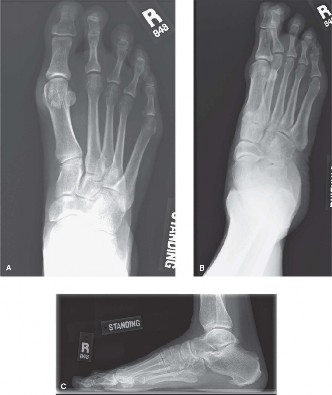

A 50-year-old male presents with 6 months of atraumatic forefoot pain. He has noticed the gradual onset of pa…